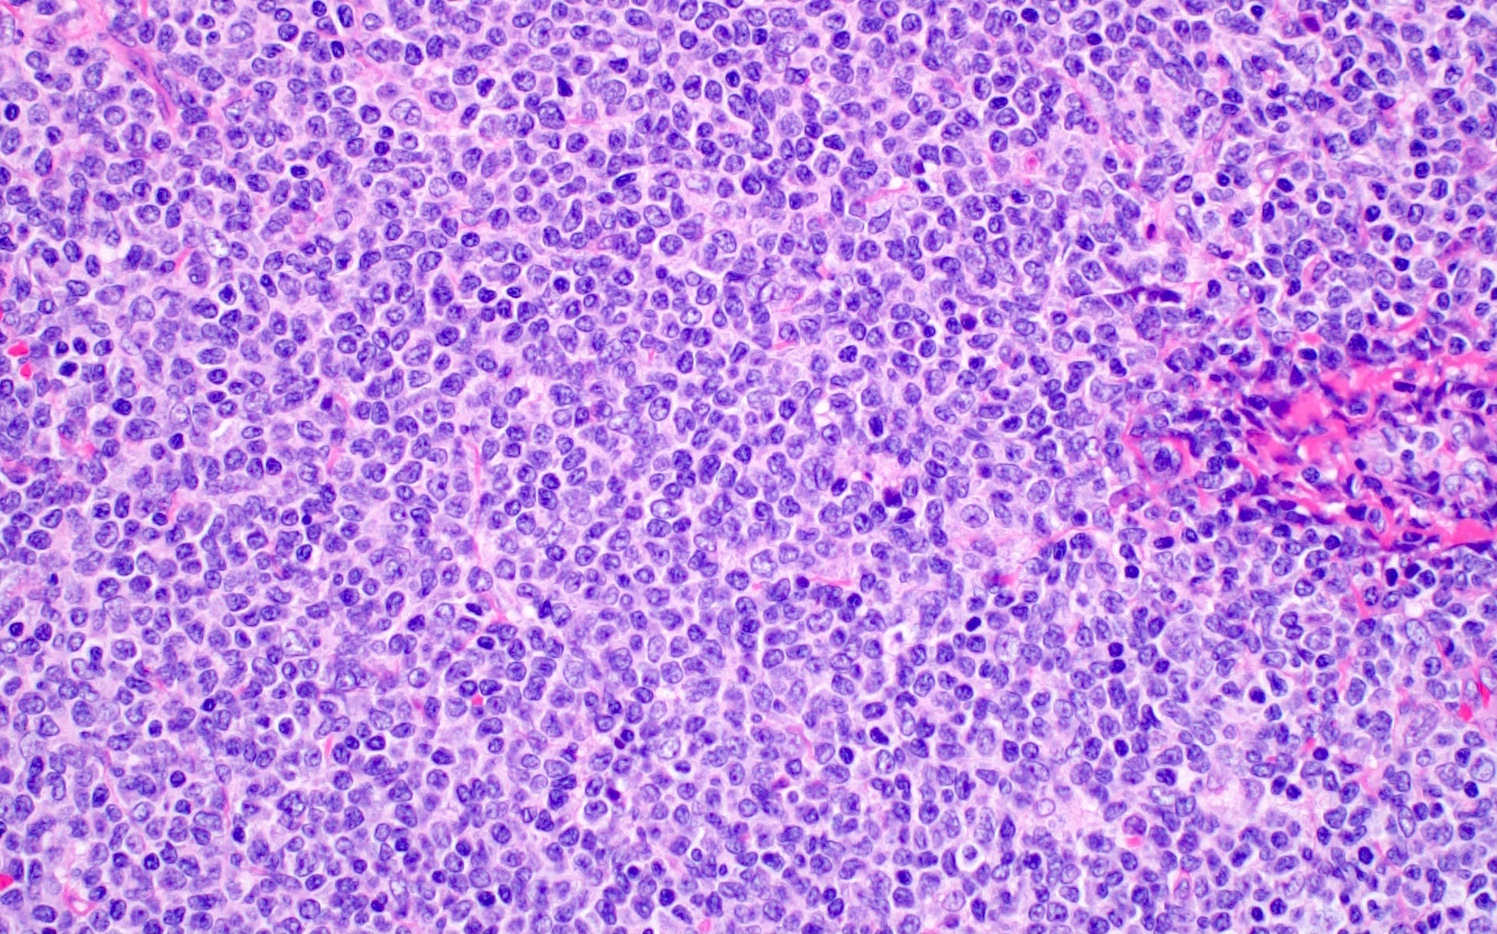

- Blastoid variant

- The growth pattern is usually diffuse

- Less frequently nodular pattern

- Starry sky appearance common in low power

- Intermediate sized cells

- Monotonous population

- Immature chromatin

- Scant cytoplasm

- High mitotic rate > 20 - 30/10 high power fields

- Resembles, in part, lymphoblastic lymphoma

Microscopic (histologic) images